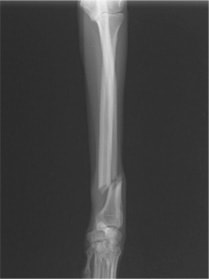

トイプードル 右遠位橈尺骨短斜骨折のALPSによる内固定